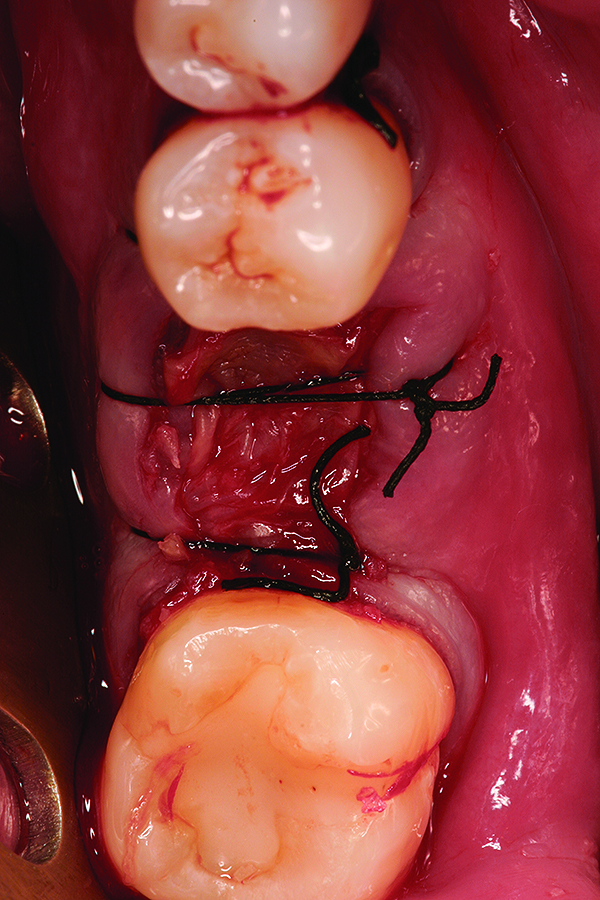

Fig 12. Note the significant formation of bone and repair of the buccal osseous defect at 3 months healing.

Figure 12

Fig 13. Placement of dental implant into healed bone. Note complete circumferential bone surrounding all aspects of the dental implant.

Figure 13